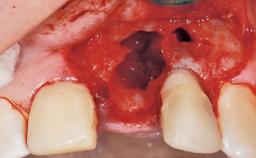

Immediate Flapless Placement of an Implant in a Maxillary Right Lateral Incisor Site

This 43-year-old male patient, a non-smoker, came to our practice because of a fracture of tooth 12 caused by a bicycle accident. Due to the combined para- and infrabony crown and root fracture, tooth extraction, and subsequent implant placement were suggested to the patient as the therapy of choice. The patient had high esthetic expectations with regard to the treatment outcome and asked for an immediate fixed provisional restoration. His individual esthetic risk profile summed up to a medium esthetic risk.

Soft Tissue Anatomy Intact Defective

Bone Volume Horizontally and vertically sufficient Horizontally deficient Deficient vertically or deficient vertically AND horizontally

Placement Protocol Immediate implant placement

Tooth Site Maxillary incisor or canine

Socket Integrity Sufficient, with intact bone walls

Bone Volume Sufficient, with intact walls